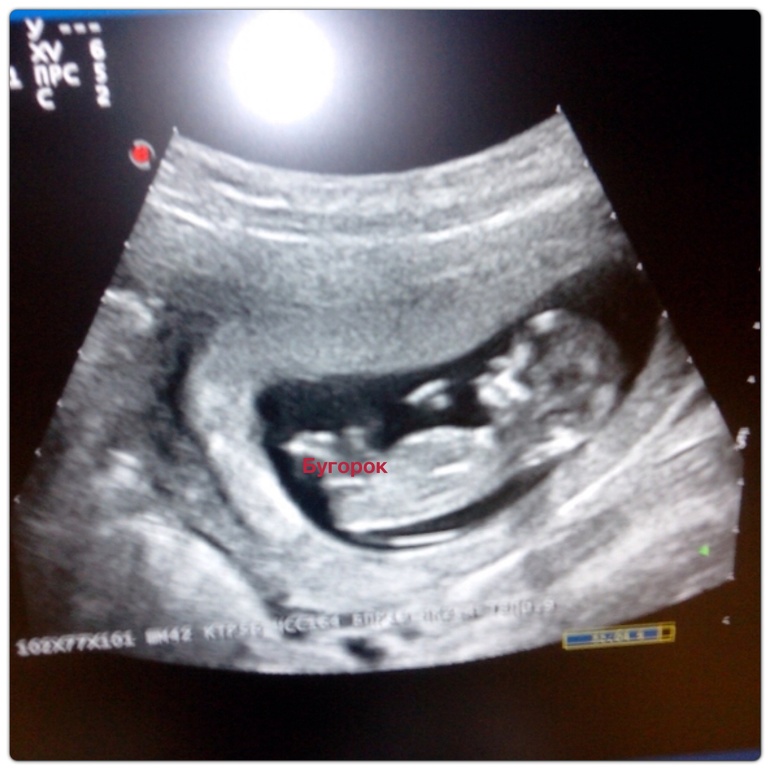

Ой,Надюха:)клево то как:)у меня аж слезы навернулись!наконец то хорошая новость в моей ленте!нет,даже отличная! И как все различают бугорки не бугорки?:))

я сама в растерянности с этими бугорками, но если честно мне это на столько не принципиально, самое главное он там такой активный - чувствует себя хорошо)))

ООО Светлана, я смотрю у вас тоже все принцессы, кроме того, кто в животике (в отличие от Нюши, которая чуть ниже меня комментила), что скажете про наши бугорки, которые писюньки?

Вот смотрите я подписала, где ваша писюлька она идет прямо в доль позвоночника. И на втором фото это чем отличаются бугорки на 12 неделях.

20.01.2014

нет все таки у тебя вверх писюн, что и соответствует картинка мальчика

на фото узи автора при проведении параллели с позвоночником больше склоняюсь к маьчику, больший процент чем девочка.

21.01.2014

Да с другой стороны какая разница кто, главное все хорошо!!! Я написала девочка потому, что у меня на всех фотках, кроме последней дочи такие бугорки были, а вот те у кого мальчики совсем по другому все.

Поздравляю вас!!! По вашей фотке и по вашему бугорку у вас девочка точно, у меня у всех такие бугорки.

а узистка сказала процентов на 80 мальчик))) Где бугорок???? ГДЕ БУГОРОК)))))) Ох у вас прям институт девиц)))))